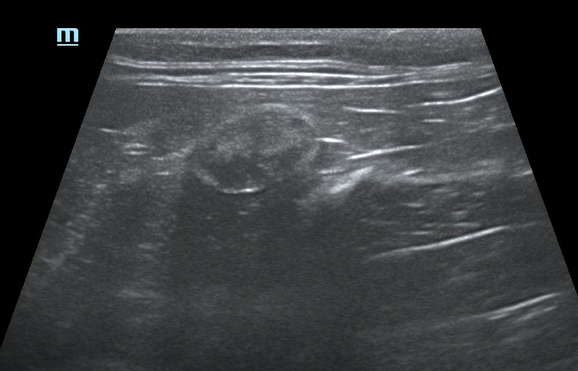

Односторонняя гипоплазия почки (рис 1), которая никак себя не проявляет, лечения не требует. Если функции пораженного органа сохранены хотя бы на 30%, то за животным ведется наблюдение, время от времени проводится обследование. При возникновении симптомов проводится симптоматическое лечение.

Рис.1. Гипоплазированная почка на он её здорово симметричной почки.